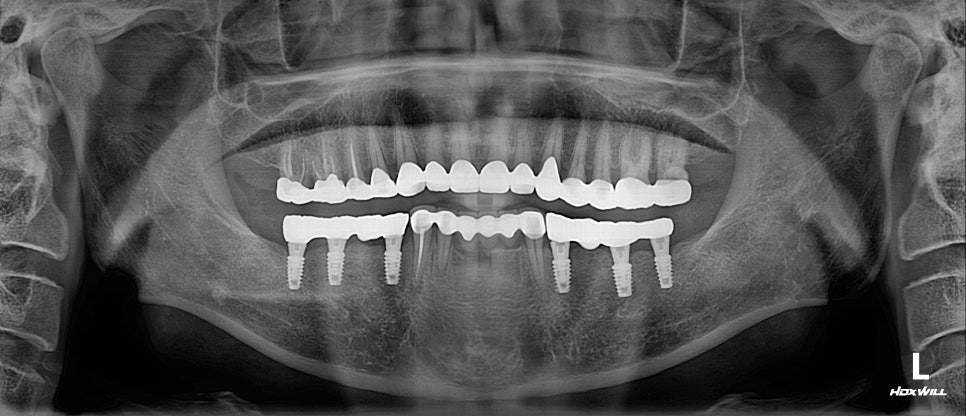

하악 임플란트 식립 후,

보철을 올리면서 정출된 어금니도 깎아

크라운을 씌우며 천천히 임시치아 쓰면서 적응 후,

조금씩 교합을 올려 교합을 맞추기로 했습니다.

이렇게 교합을 올리는 것을

“교합 거상”이라고 부릅니다 ^^

본래의 교합처럼 회복시켜드리기 위해

최종 보철물 제작까지 꼼꼼히 진행해 드렸고,

환자분께서 잘 따라와 주신 덕분에

치료를 잘 마무리해 드렸습니다 😊